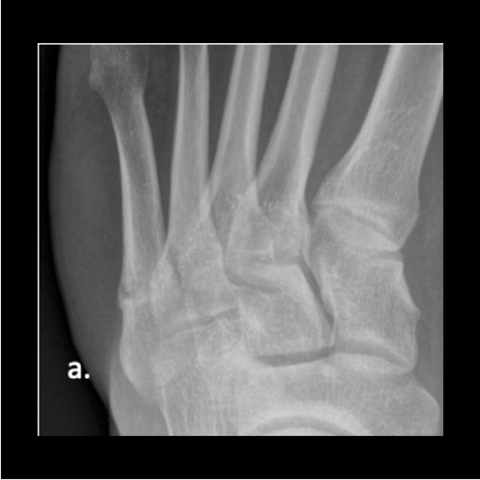

Figure 4a

Figure 4a. A 24-year-old male soldier refractured 1 year after his original surgery. He had returned to Airborne status with at least 15 jumps since his original surgery, with no issues running. Here is the 24-year-old soldier’s foot 6 months post-surgery.